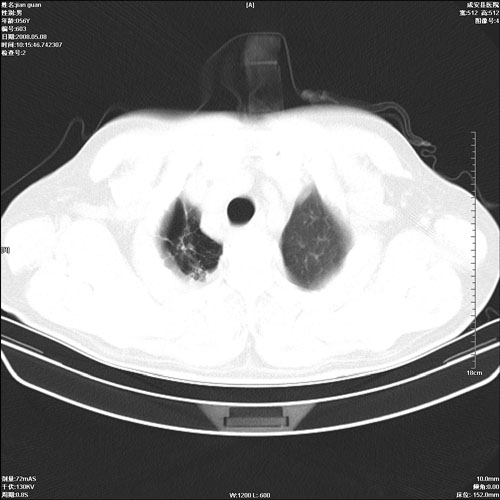

病人 男 60岁 主诉 胸闷 无明显发热 一般情况尚可。

两上肺陈旧性结核;慢支肺气肿、伴感染?

1.右上肺陈旧性肺结核.

1.两上肺陈旧性结核;慢支肺气肿。

考虑.两上肺陈旧性结核;慢支肺气肿。肺心病

两上肺陈旧性结核,慢支肺气肿。

1.陈旧肺结核;

2.慢支肺气肿;